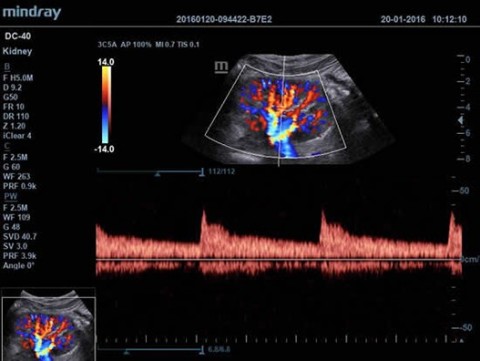

- Режимы сканирования B/M/Цветовой доплер CDI/Цветной M/Энергетический доплер PD/Направленный энергетический доплер Dir.PD

- Импульсно-волновой доплер (включая режим высокой частоты повторения импульсов HPRF)

Доплер:

Да